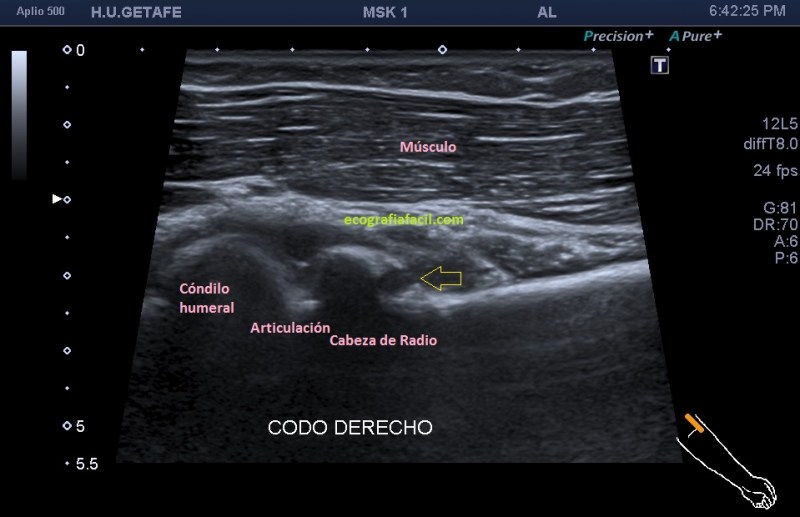

En la imagen 3 te muestro detalladamente la articulación de la cabeza del radio con el epicóndilo y puedes ver, de nuevo como la articulación está ocupada por una moderada cantidad de contenido anecoico en relación con presencia de líquido articular. Se observa el cartílago articular del epicóndilo (hipoecogénico) delimitado por una línea hiperecogénica donde reposa el líquido articular, entre éste y la cortical curva del epicódilo.

3